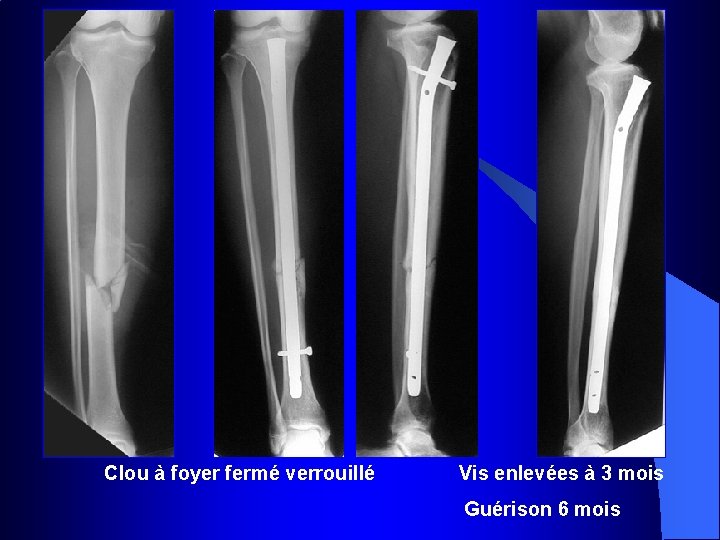

Clou à foyer fermé verrouillé Vis enlevées à 3 mois Guérison 6 mois